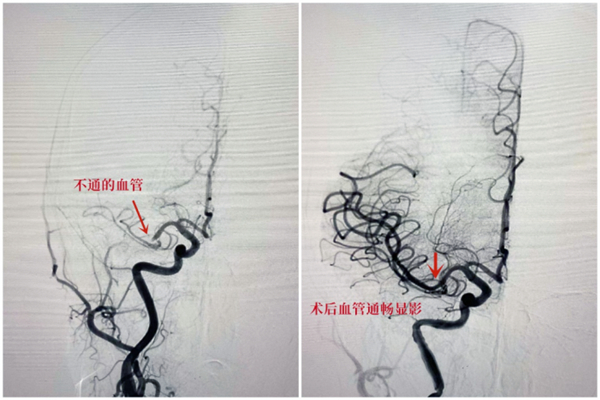

多学科接力!深圳二院脑卒中急诊绿色通道,为患者开启生命之门

脑卒中,是目前我国致死第一的重大疾病,发病人数在逐年上升,时间窗内溶栓取栓是减少残疾改善预后最主要的手段。但是这个时间窗仅有几个小时,用“时间就是大脑”来形容抢救脑卒中患者对时间和速度的要求并不为过。